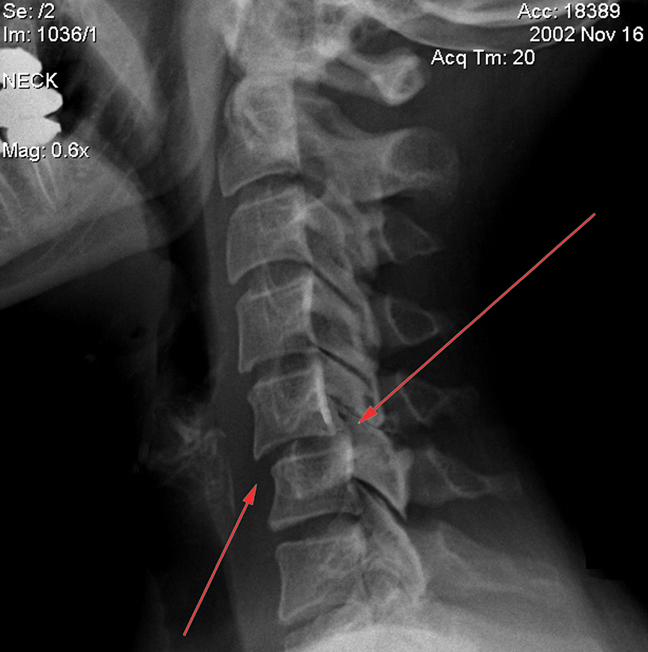

Методы диагностики подвывихов, помимо консультаций специалистов, таких как невролог и ортопед, включают ряд аппаратных исследований:

- рентгенография;

- компьютерная томография (КТ);

- магнитно-резонансная томография (МРТ).

Рентген шейного отдела позвоночника выполняется в трех проекциях: два боковых снимка в положении сгибания и разгибания шеи, а также один снимок через ротовую полость.

Компьютерная томография позволяет оценить высоту межпозвоночного диска и выявить возможные смещения. Этот метод особенно важен при диагностике подвывиха первого шейного позвонка (С1), особенно в случаях асимметрии между зубовидным отростком и атлантом.